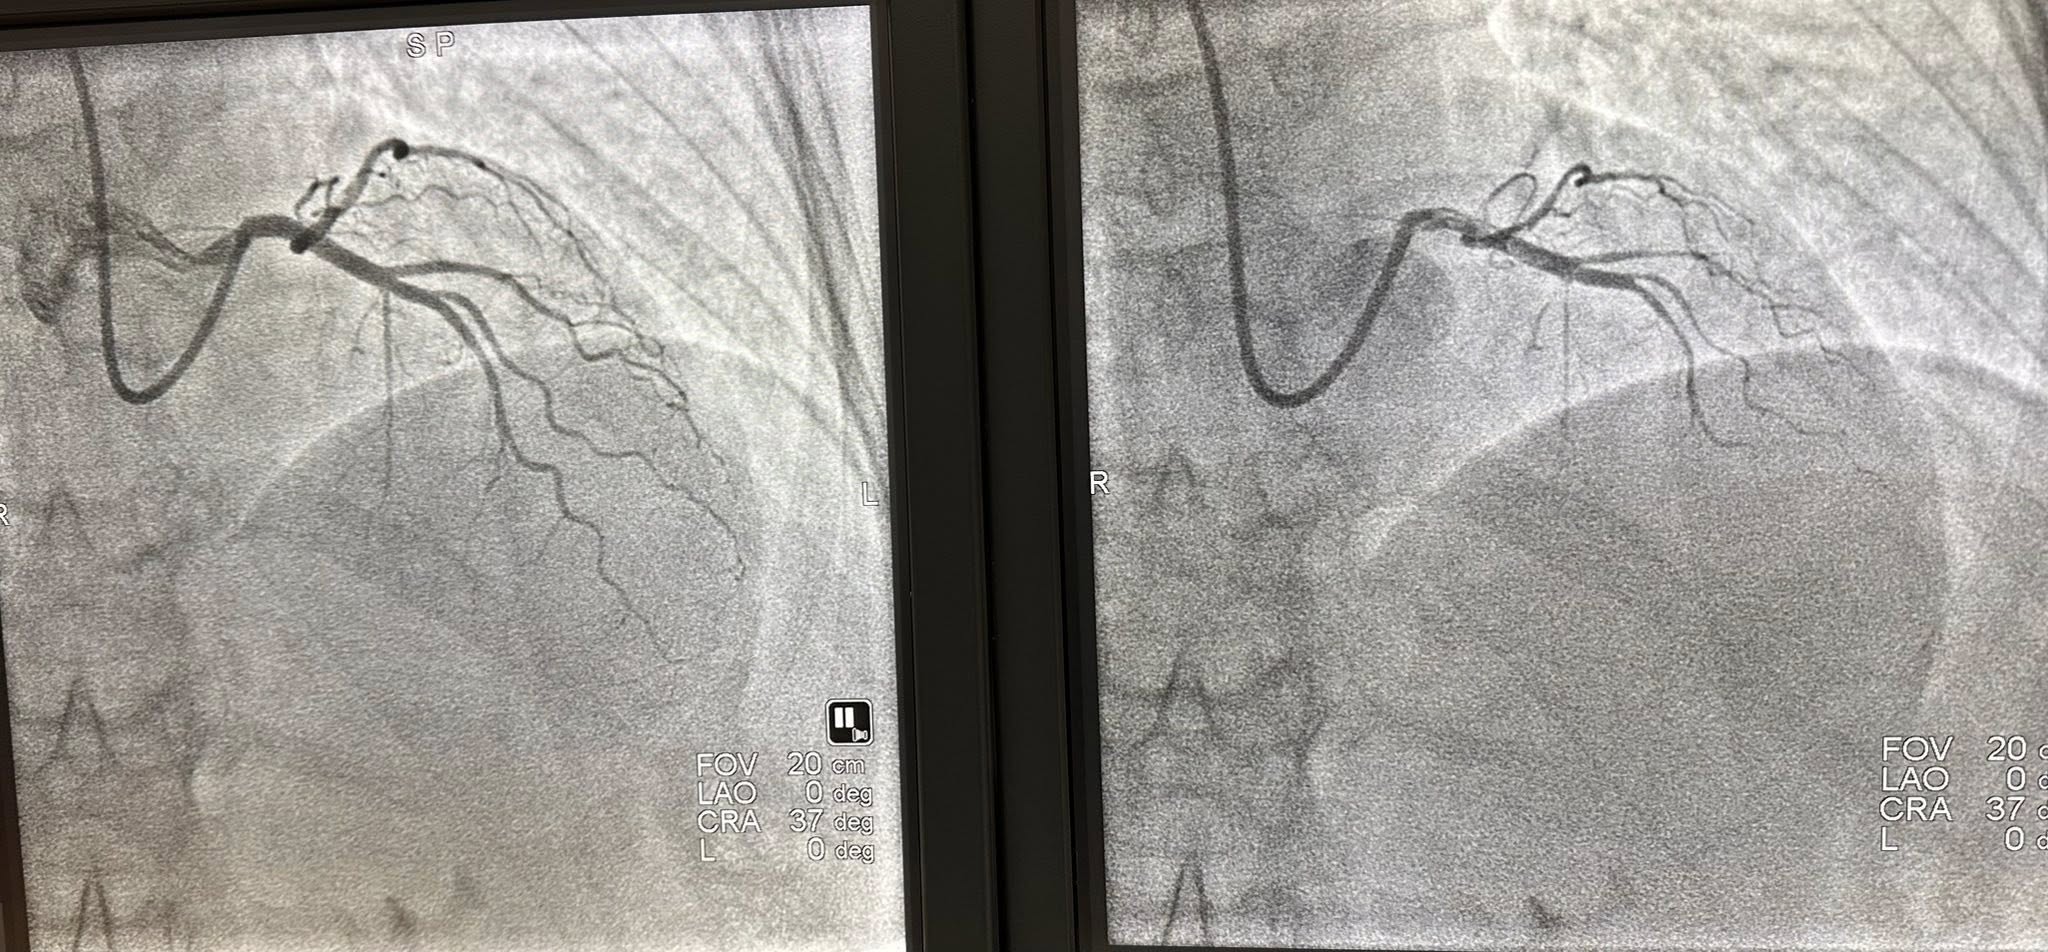

“Danas smo obavili dva slučaja kompletne invazivne koronarne fiziologije i kod jednog pacijenta potvrdili dijagnozu vazospastične angine. Ponosan sam na tim i zahvalan svom mentoru, dr Ivanu Iliću, kao i kompaniji “Abbott Medical“ na podršci’“, izjavio je dr Aleksandar Janjičić, načelnik Odjeljenja za internističke grane JZU Bolnica “Sveti Vračevi“ Bijeljina.

On je naglasio da je ovo značajan napredak za pacijente iz cijele regije, jer se sada dijagnostičke procedure koje su do sada bile dostupne samo u referentnim centrima van zemlje, mogu obaviti i u Bijeljini.

„Izvođenjem današnjih procedura JZU Bolnica „Sveti Vračevi“ u Bijeljini je postala dio registra centara jugoistočne Evrope za ispitivanje fiziologije krvnih sudova srca“, naglasio je dr Janjičić.